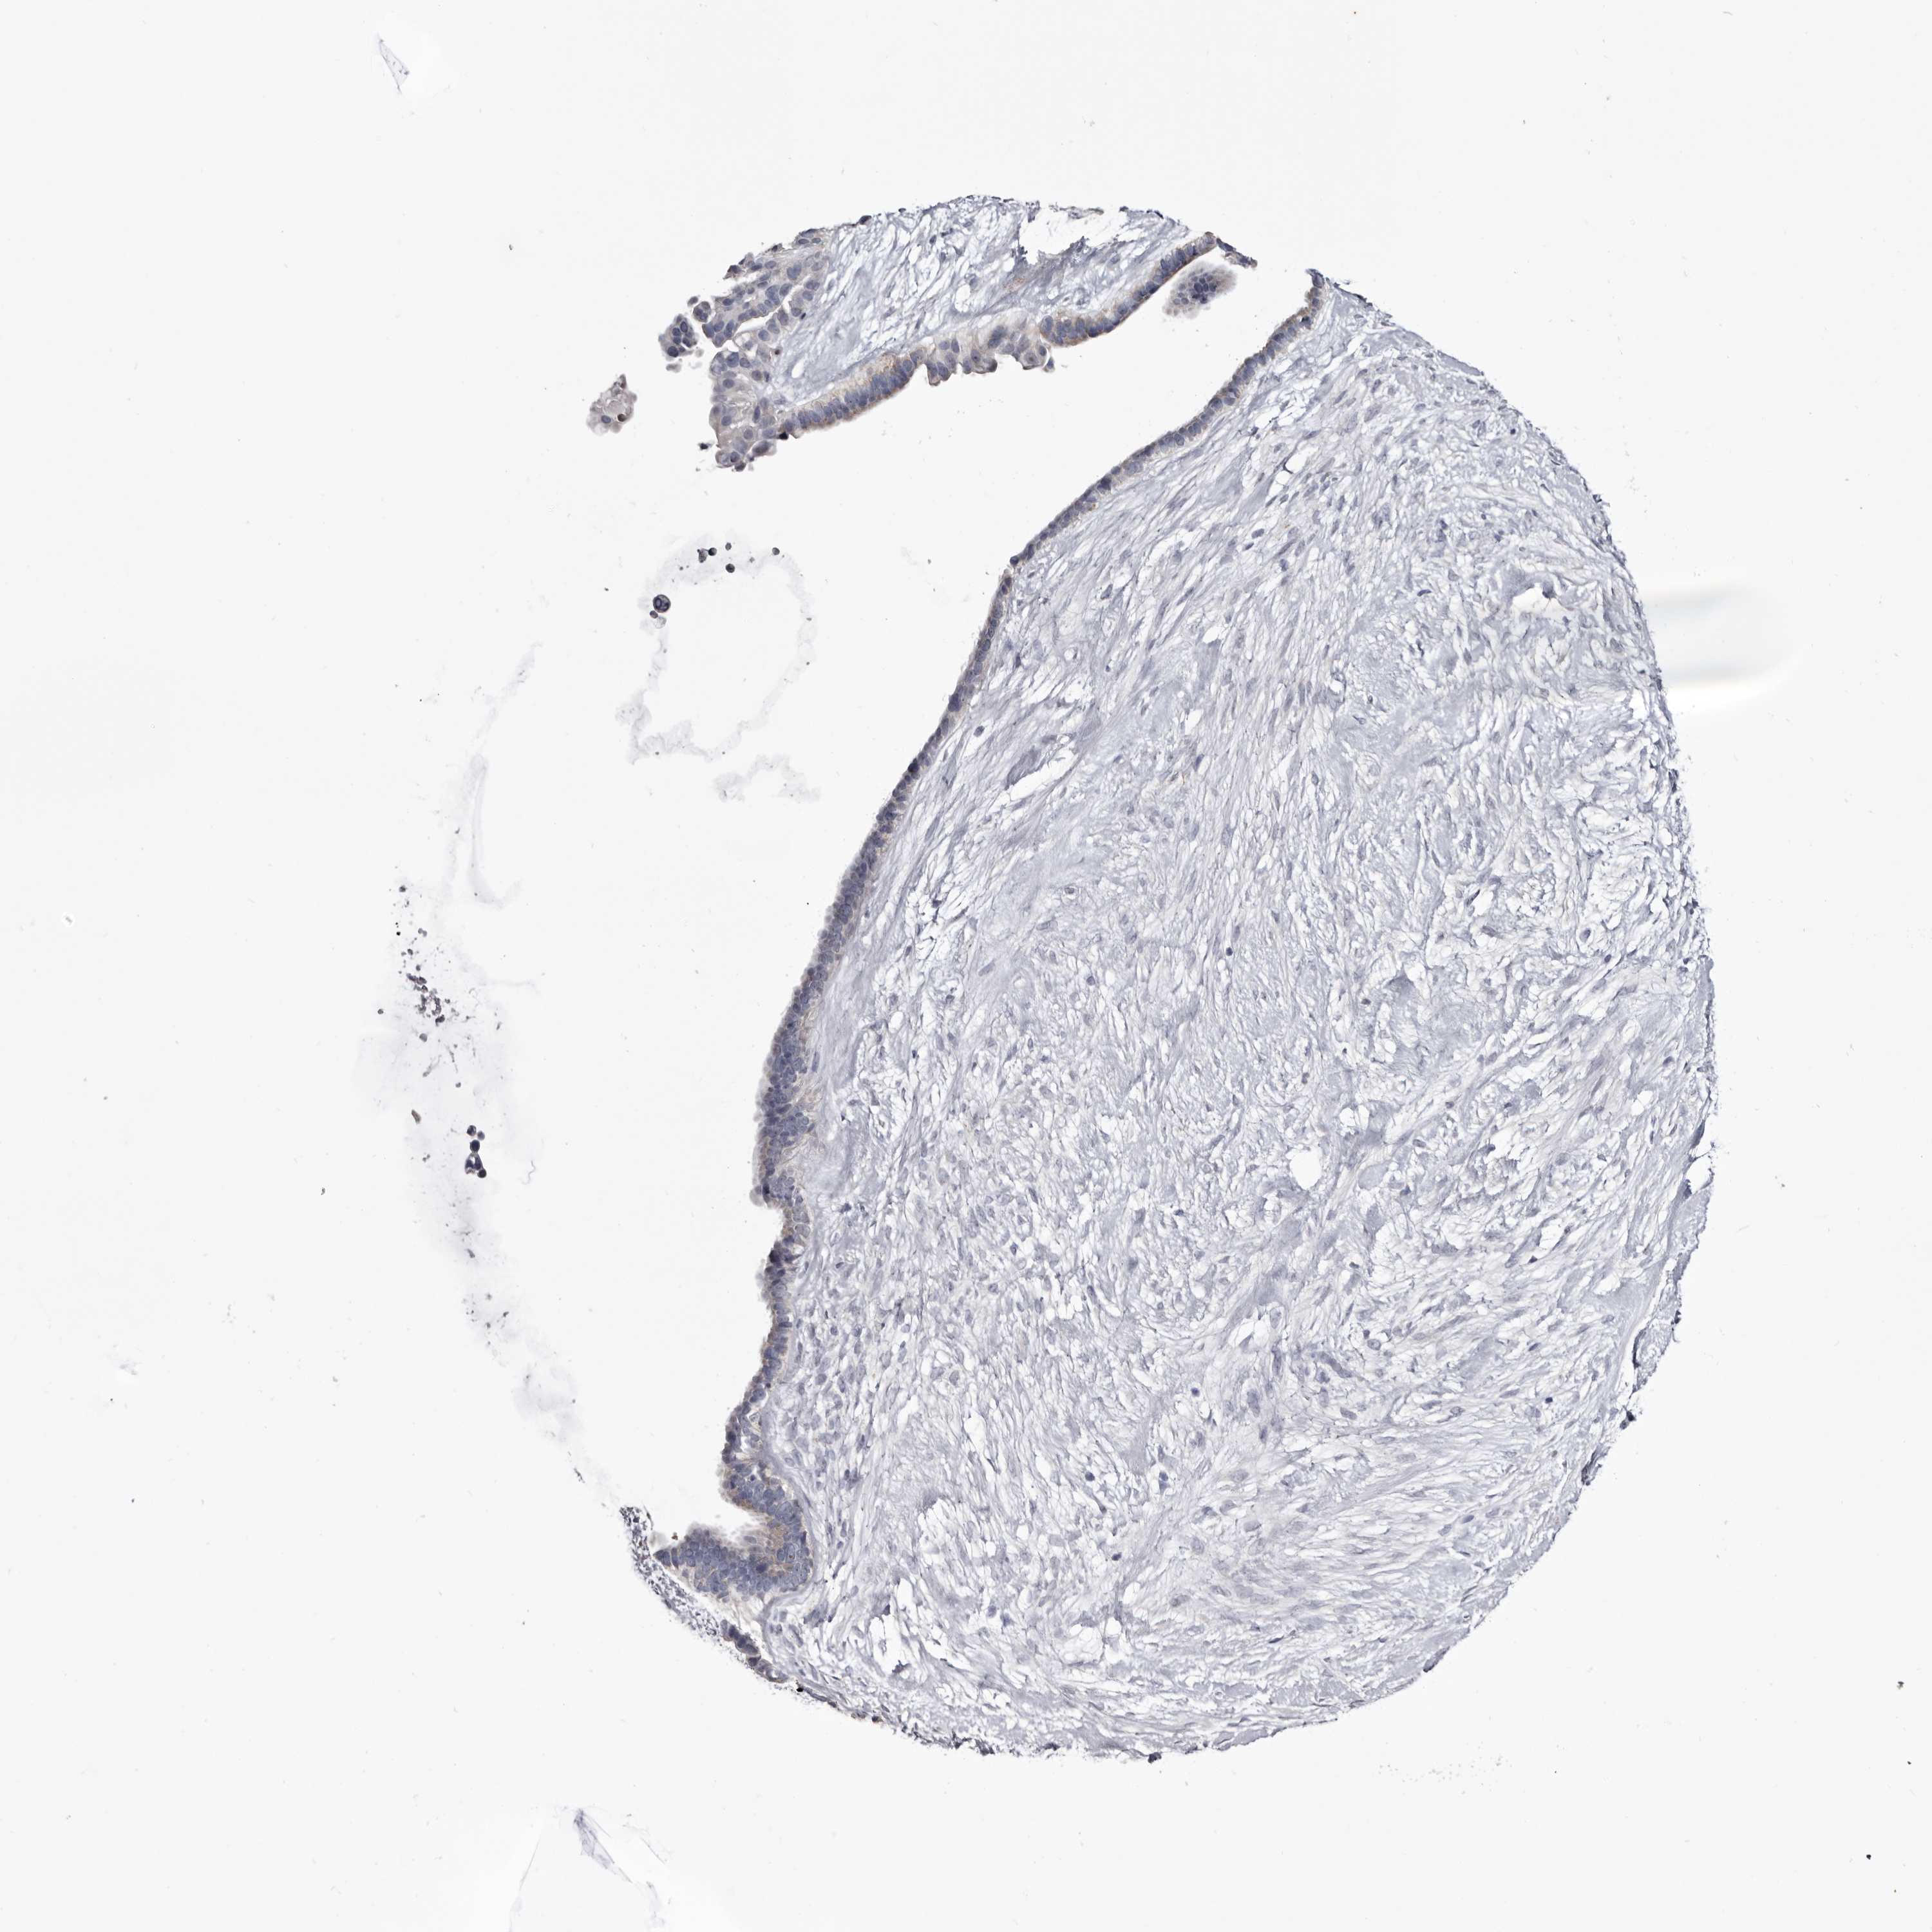

OVARIAN CANCER - Protein expressioni

A mouse-over function shows sample information and annotation data. Click on an image to view it in a full screen mode. Samples can be filtered based on level of antibody staining by selecting one or several of the following categories: high, medium, low and not detected. The assay and annotation is described here.

Note that samples used for immunohistochemistry by the Human Protein Atlas do not correspond to samples in the TCGA dataset.

Antibody stainingi

Antibody staining in the annotated cell types in the current human tissue is reported as not detected, low, medium, or high, based on conventional immunohistochemistry profiling in selected tissues. This score is based on the combination of the staining intensity and fraction of stained cells.

Each image is clickable and will lead to virtual microscopy that enables deeper exploration of all samples and also displays staining intensity scores, fraction scores and subcellular localization as well as patient and tissue information for each sample.

Antibody HPA007845

Antibody HPA026823

Antibody CAB015170

Cystadenocarcinoma, serous, NOS

Carcinoma, endometroid

Cystadenocarcinoma, mucinous, NOS

Carcinoma, NOS